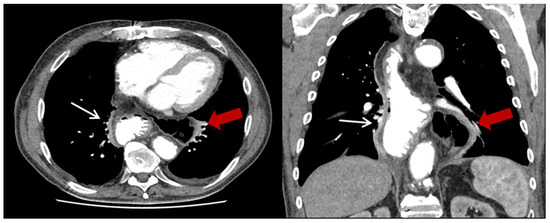

| Characteristics | HH (n = 23) (%) |

| Content of HH, n (%) | |

| Colon | 23 (100) |

| Additionally small bowel | 3 (13) |

| Position of the HH n (%) | |

| Left thoracic side | 18 (78.3) |

| Right thoracic side | 1 (4.4) |

| Both sides | 1 (4.4) |

| Lower mediastinum | 3 (13) |